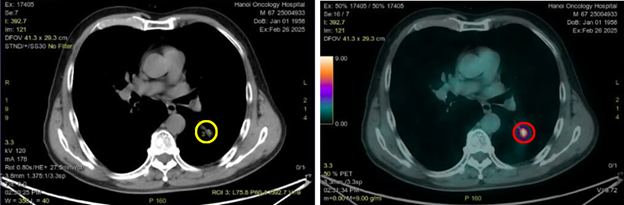

Hình 4: Hình ảnh tổn thương u phổi thùy dưới phổi trái kích thước 10x15mm trên CT (vòng tròn màu vàng) và PET/CT (vòng tròn màu đỏ) tăng chuyển hóa FDG (SUVmax: 9,8)

- Như vậy đây là trường hợp bệnh nhân ung thư phổi với mô bệnh học: ung thư biểu mô tuyến, với kích thước tổn thương nguyên phát nhỏ, trên hình ảnh CT ngực thấy hình ảnh hạch trung thất ở cửa sổ chủ phổi và không phát hiện các tổn thương nghi ngờ thứ phát tại các cơ quan khác.

- Sau khi chụp PET/CT để đánh giá giai đoạn trước điều trị phát hiện tổn thương thứ phát tại xương ức và xương chậu phải, dù trên hình ảnh CT không phát hiện sự biến đổi về mặt cấu trúc tương ứng với vị trí các xương này. Về mặt lý thuyết sự biến đổi về mặt chức năng thường xảy ra trước khi có sự biến đổi về mặt cấu trúc với thời gian khoảng 6 tháng.

- Việc ghi hình PET/CT giúp phát hiện và định vị chính xác vị trí tổn thương di căn từ đó giúp xác định chính xác giai đoạn bệnh. Đối với trường hợp bệnh nhân trên nếu chỉ dựa trên kết quả chụp chiếu CT đơn thuần sẽ bỏ sót các tổn thương thứ phát ở xương. Việc chụp PET/CT giúp phát hiện các tổn thương di căn tại vị trí xương ức và xương chậu dẫn tới sự thay đổi về hướng điều trị, cu thể trên bệnh nhân này không còn chỉ định phẫu thuật hay xạ trị triệt căn nữa và sẽ tiến hành điều trị toàn thân và chăm sóc giảm nhẹ.